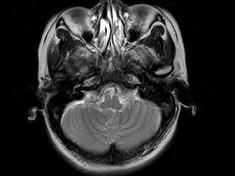

女,41岁,阵发性头痛伴恶心、呕吐20余天,CT影像如图,最可能的诊断为 ( )

• A.双侧筛窦息肉

• B.双侧筛窦息真菌感染

• C.双侧筛窦过敏性炎症

• D.双侧筛窦炎

• E.双侧筛窦未见明显异常

答案: D